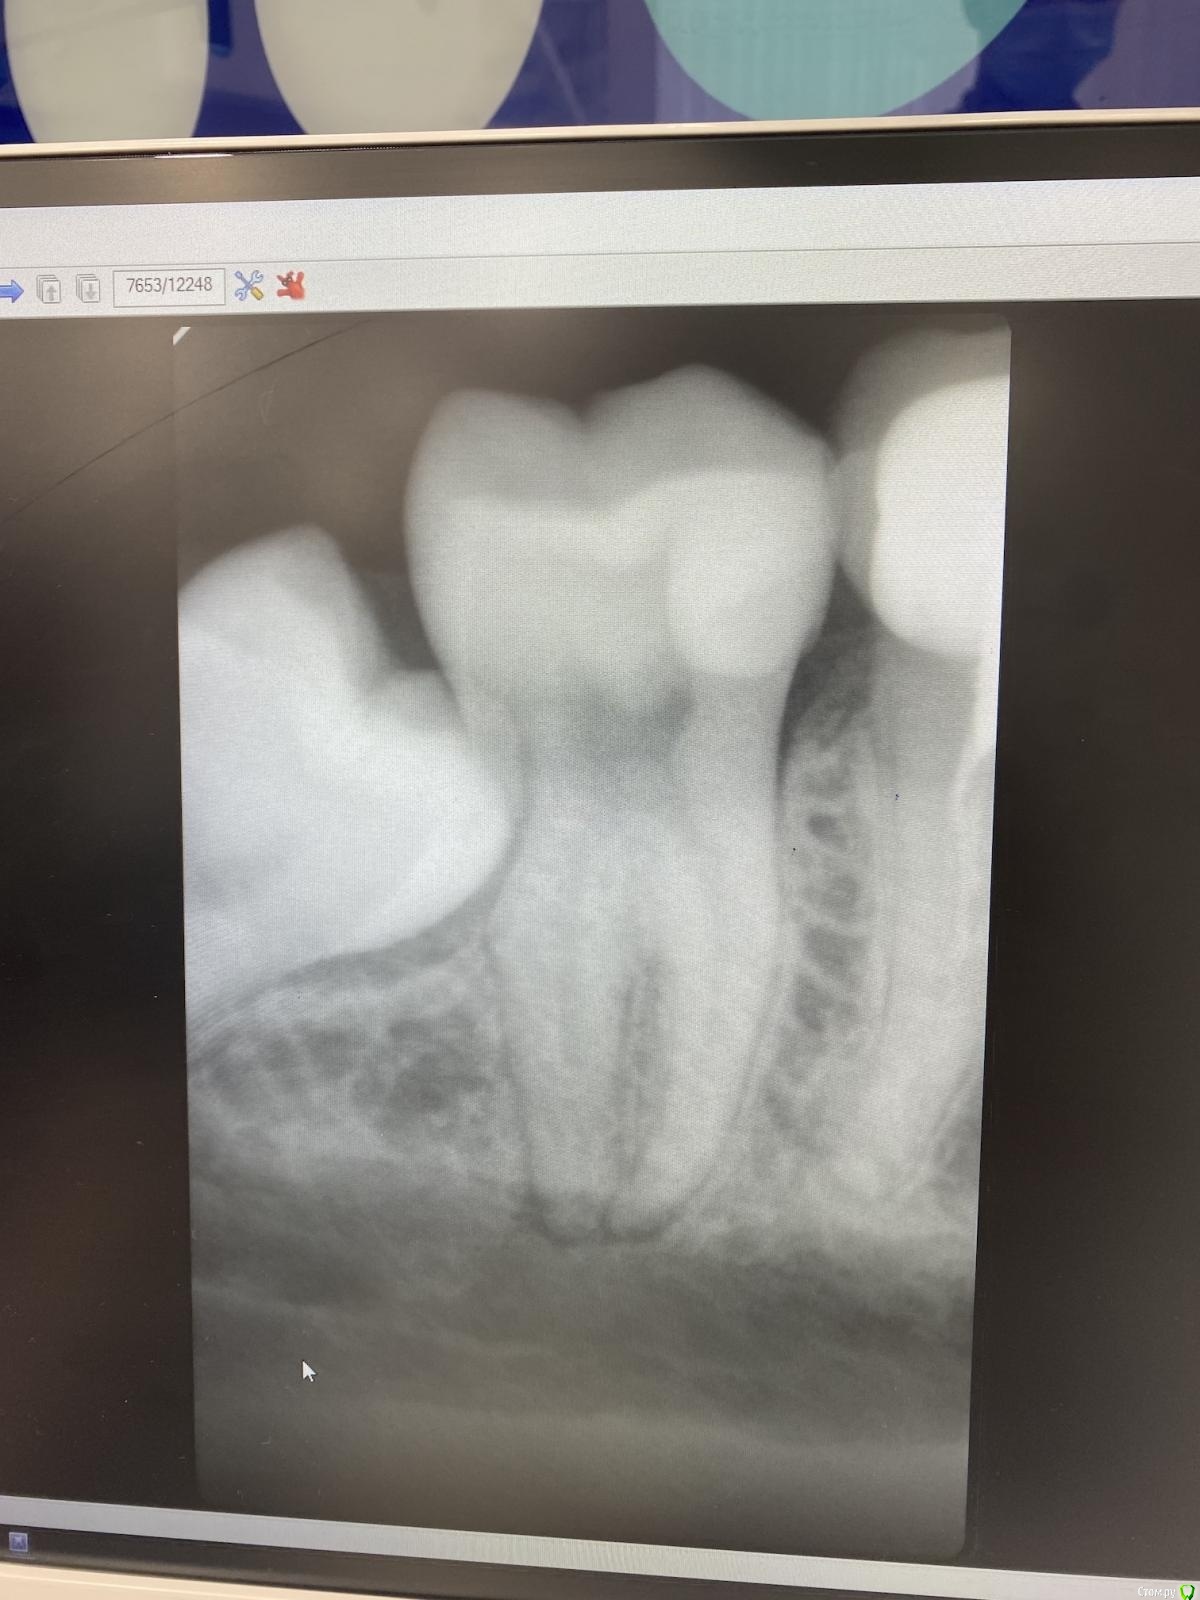

Sandro1 Опубликовано 4 марта, 2021 Поделиться Опубликовано 4 марта, 2021 (изменено) Здравствуйте, дорогие стоматологи! Хотелось бы узнать ваше мнение вот по такому вопросу. Ходила сегодня к хирургу и если честно он меня ошарашил , я думала, что надо будет удалять только 1 зуб мудрости, но он сказал, что скорее всего и 7ку тоже.... Порешили, что пока этого делать не будем, но в будущем, конечно придется... и по ходу имплантация неизбежна. Что бы вы могли посоветовать? А может быть еще есть шанс спасти 7ку или уже совсем никак? Зуб мудрости немного торчит сверху, но еда не забивается и вообще-то никак не проявляет себя особо. Сможет ли еще костная ткань нарасти? или уже все? Изменено 4 марта, 2021 пользователем Sandro1 Ссылка на комментарий

annda Опубликовано 4 марта, 2021 Поделиться Опубликовано 4 марта, 2021 Сделайте КТ этого сектора и будет яснее судьба 7ки. Скорее всего, на двухмерном снимке проекции двух зубов накладываются одна на другую.Посоветуйтесь еще с парой врачей. 2 Ссылка на комментарий

АнтонТЛТ Опубликовано 4 марта, 2021 Поделиться Опубликовано 4 марта, 2021 а если они вдруг есть, то можно что-то сделать? может ли рентген это показать?или может быть пока не трогать?Есть варианты спасения таких зубов.Доктор Annda, верно написала. КЛКТ даст больше информации. 1 Ссылка на комментарий

Irouil Опубликовано 4 марта, 2021 Поделиться Опубликовано 4 марта, 2021 Судя по той картине, что показывает предоставленный снимок, непоправимого ущерба 7ке не нанесено. Соглашусь с Антоном - удалить, осмотреть. Я в таких ситуациях обязательно провожу герметичное ушивание раны, что нельзя назвать ортодоксальным методом, но в моей практике позволяет оптимизировать костную регенерацию по задней стенке корня 7-го зуба 1 Ссылка на комментарий